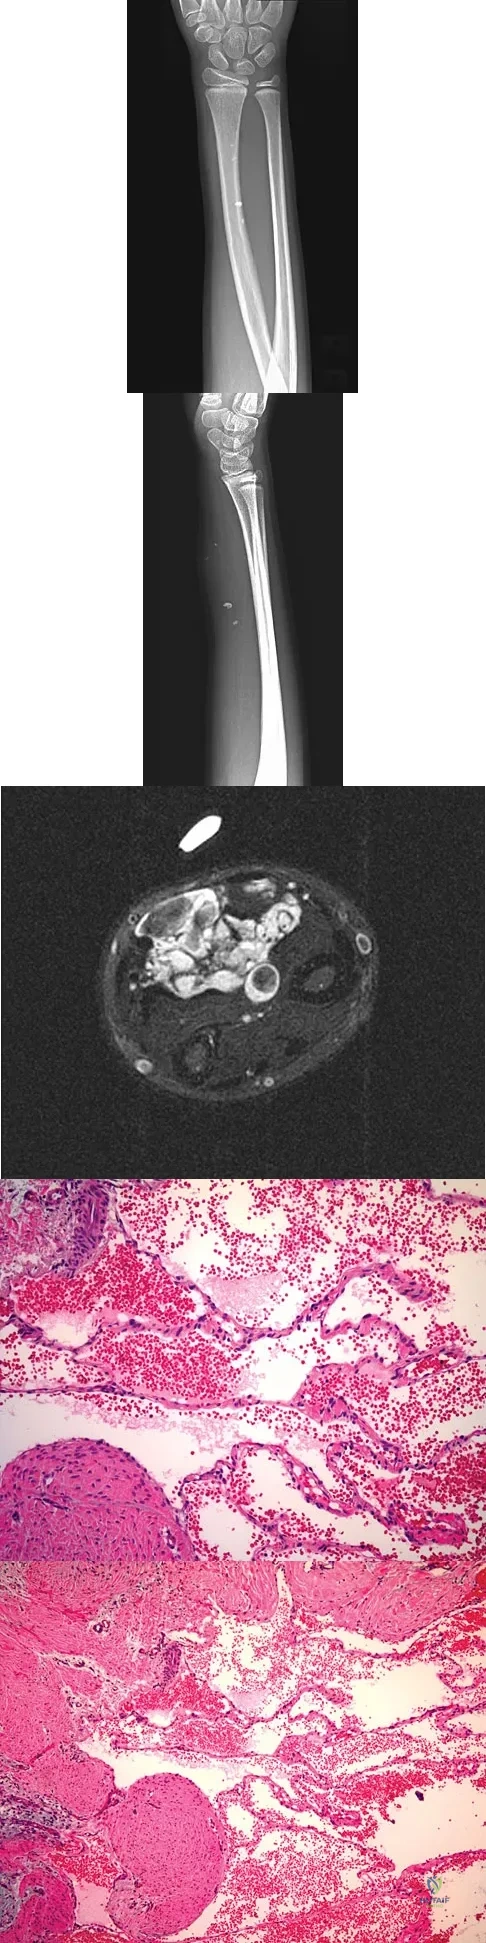

A 7-year-old girl has had a painful forearm for the past 2 months. Examination reveals fullness on the volar aspect of the forearm. Radiographs and an MRI scan are shown in Figures 42a through 42c. Biopsy specimens are shown in Figures 42d and 42e. What is the most likely diagnosis?

Explanation